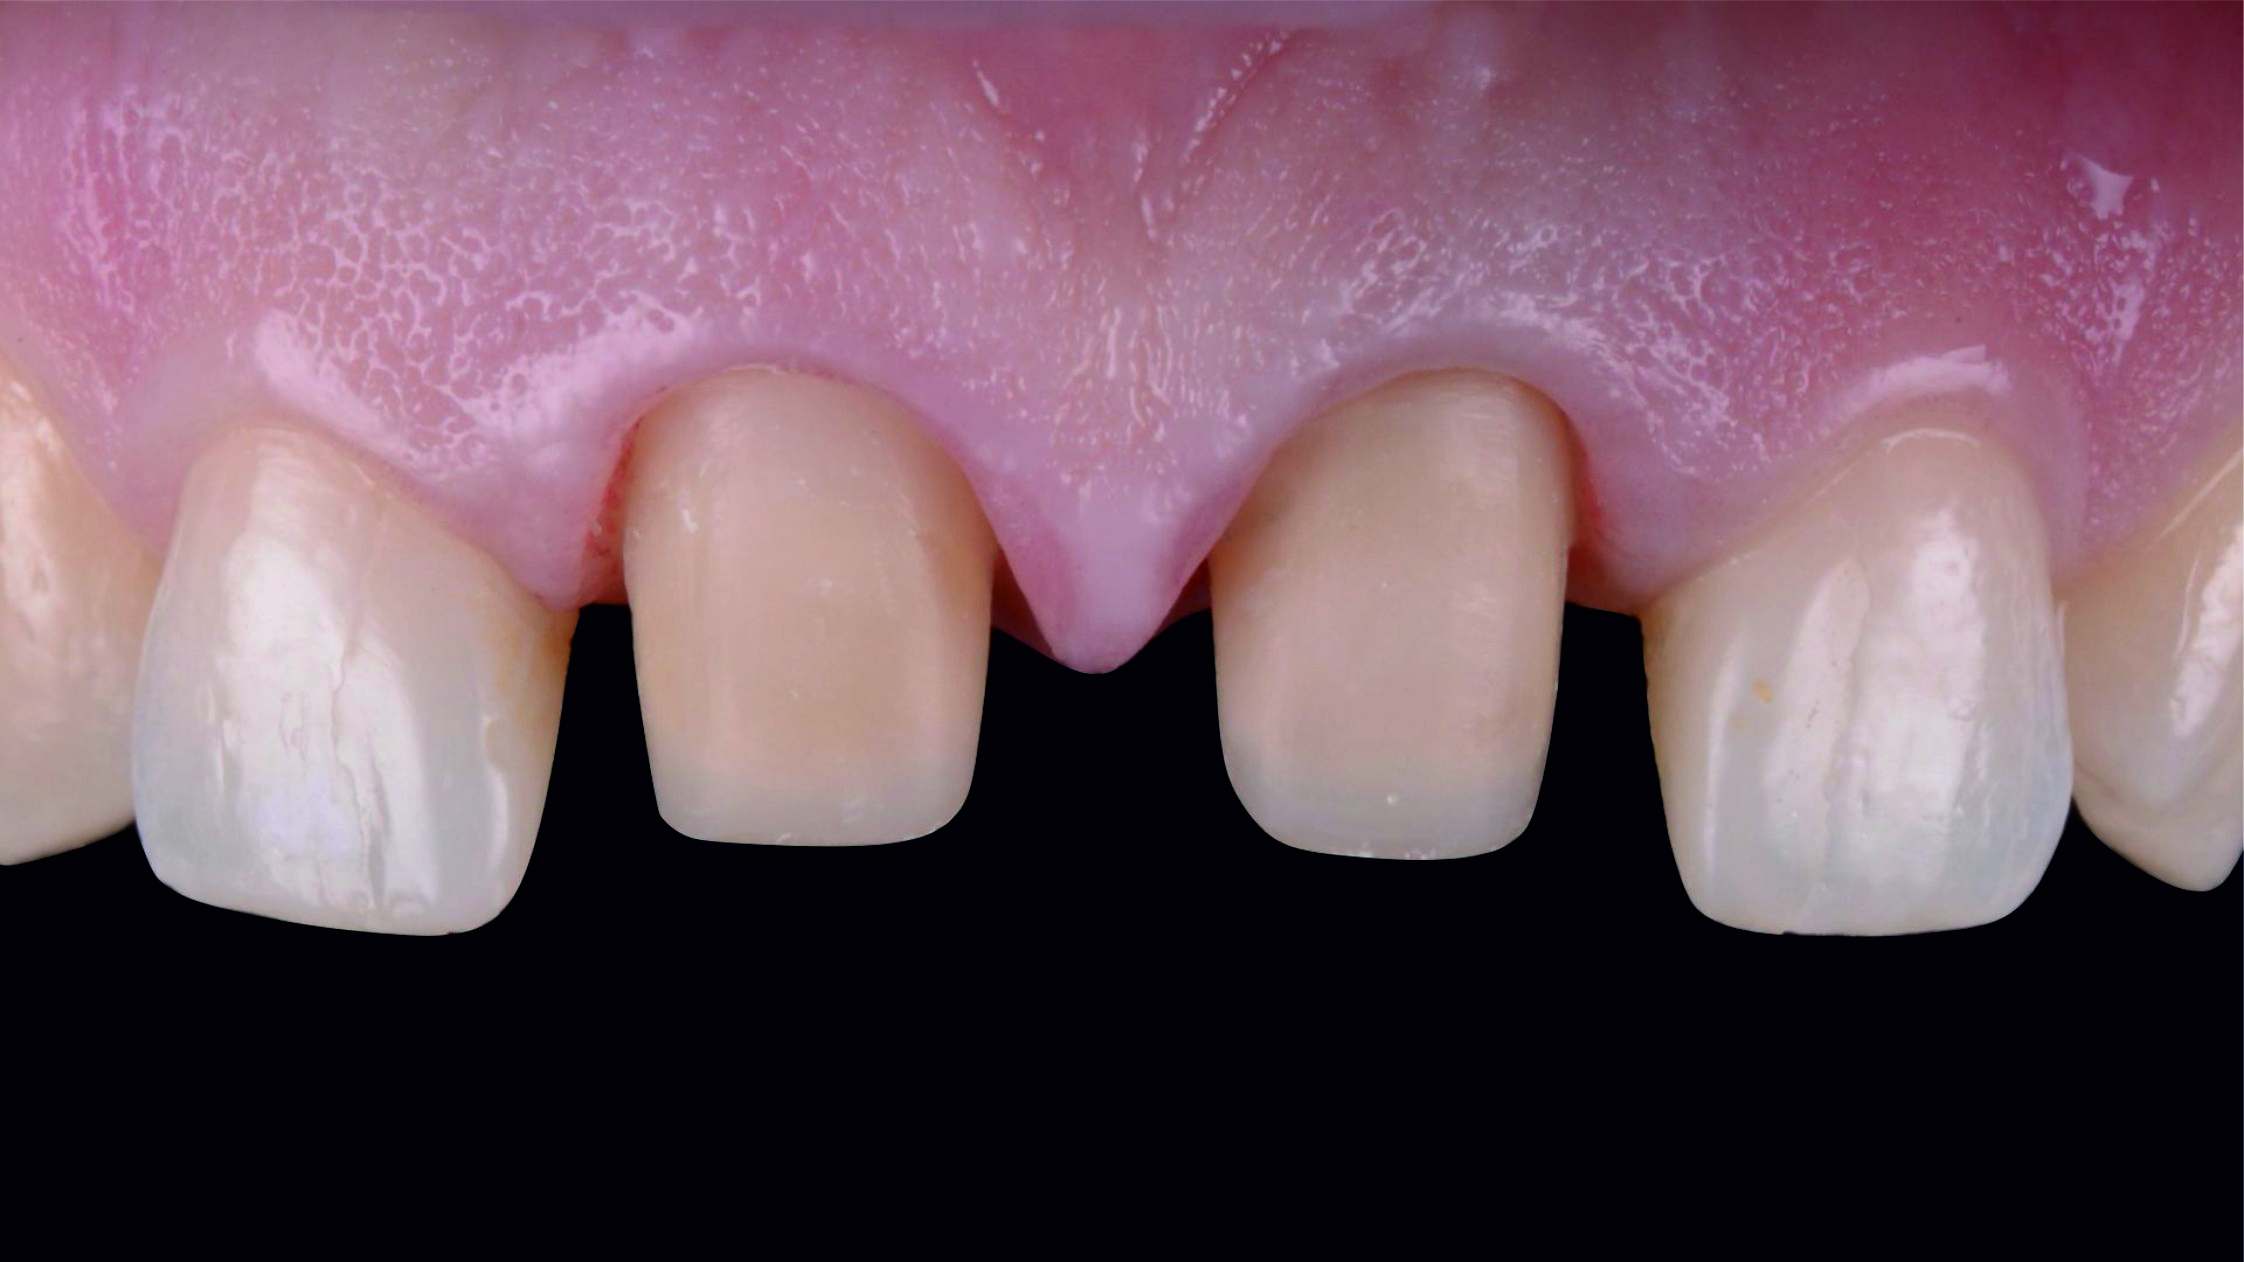

Фото 1. Початкова ситуація: жінка віком приблизно 35 років, із двома металокерамічними коронками, встановленими на верхніх центральних різцях.

Основні скарги: асиметрія центральних різців, запалення й кровоточивість ясен навколо коронок, загальне невдоволення естетикою цієї зони.

Фото 2. Через високо розташовану лінію посмішки можна припустити, що будь-яка вада після лікування обов'язково буде дуже добре помітною.